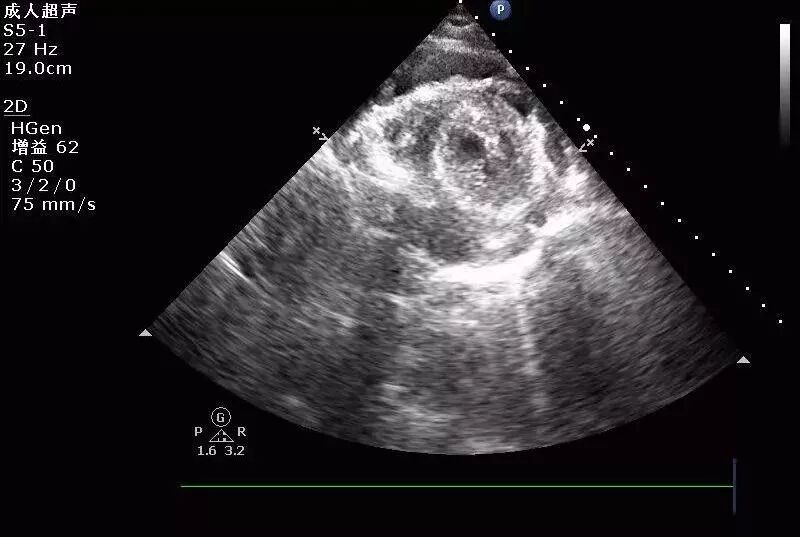

图1和图2 :术中行心包积液彩超可见:心包腔内见液性暗区:右房顶部  20mm,右室前壁最多时25 mm,右室侧壁旁15 mm。提示:心包积液(中大量)。

图3和图4: 彩色多普勒:心包腔可见可疑的较明亮彩色信号。